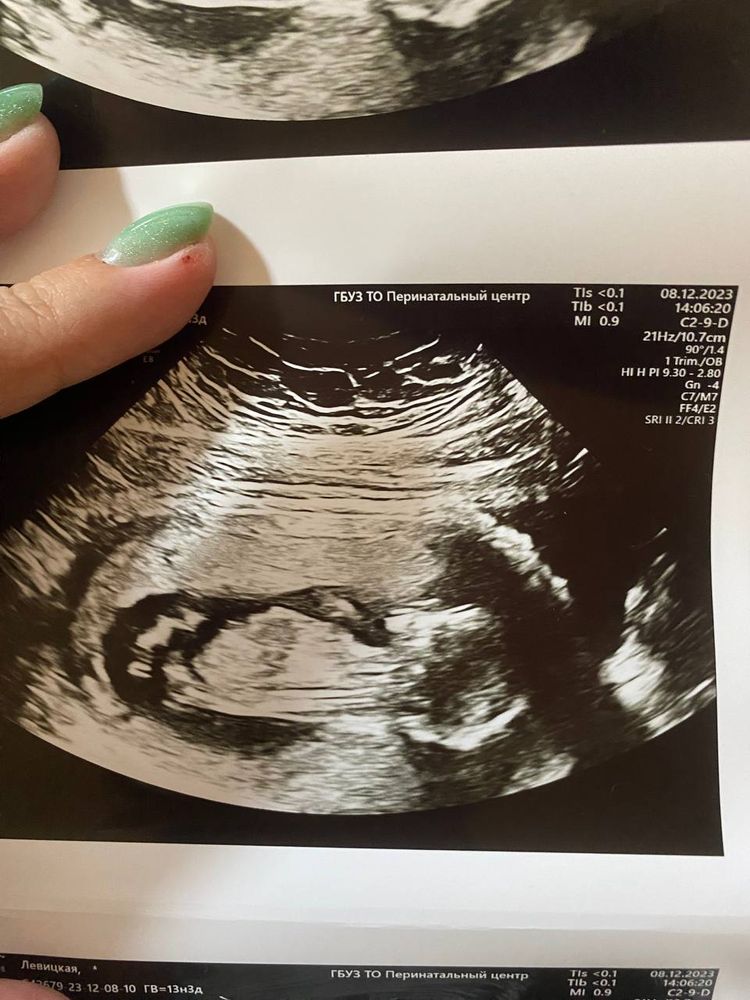

Пол сказали, что лучше смотреть на втором скрининге, но кому-то говорили и на первом. Фото прикладываю, может есть любители, как я, гадать по фото!)))

Мне кажется, что девочка

Юлия Мать Драконов

а мне на втором снимке видется мальчик! но самое главное,чтобы малыш был здоров! легкой беременности вам!

Юлия Мать Драконов, теперь я тоже вижу очертания пениса)))) Спасибо за добрые слова!